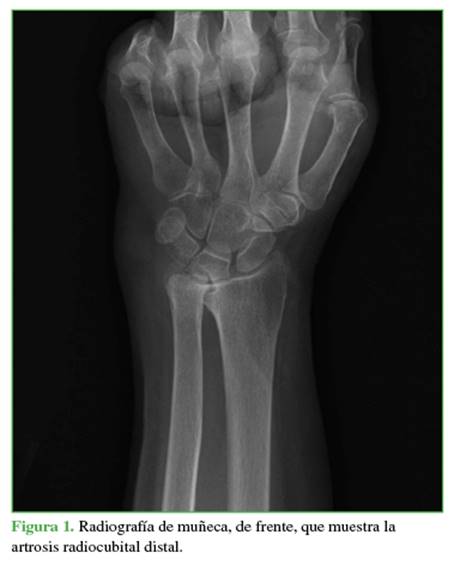

El protocolo de tratamiento fue el siguiente: la primera consulta por dolor en la articulación RCD de la muñeca incluyó una anamnesis sobre el mecanismo del trauma inicial o enfermedad degenerativa y luego un examen clínico. Se emplearon la prueba de Nakamura y la prueba del destornillador (screwdriver test) y se tomó una radiografía de muñeca, de frente (Figura 1).